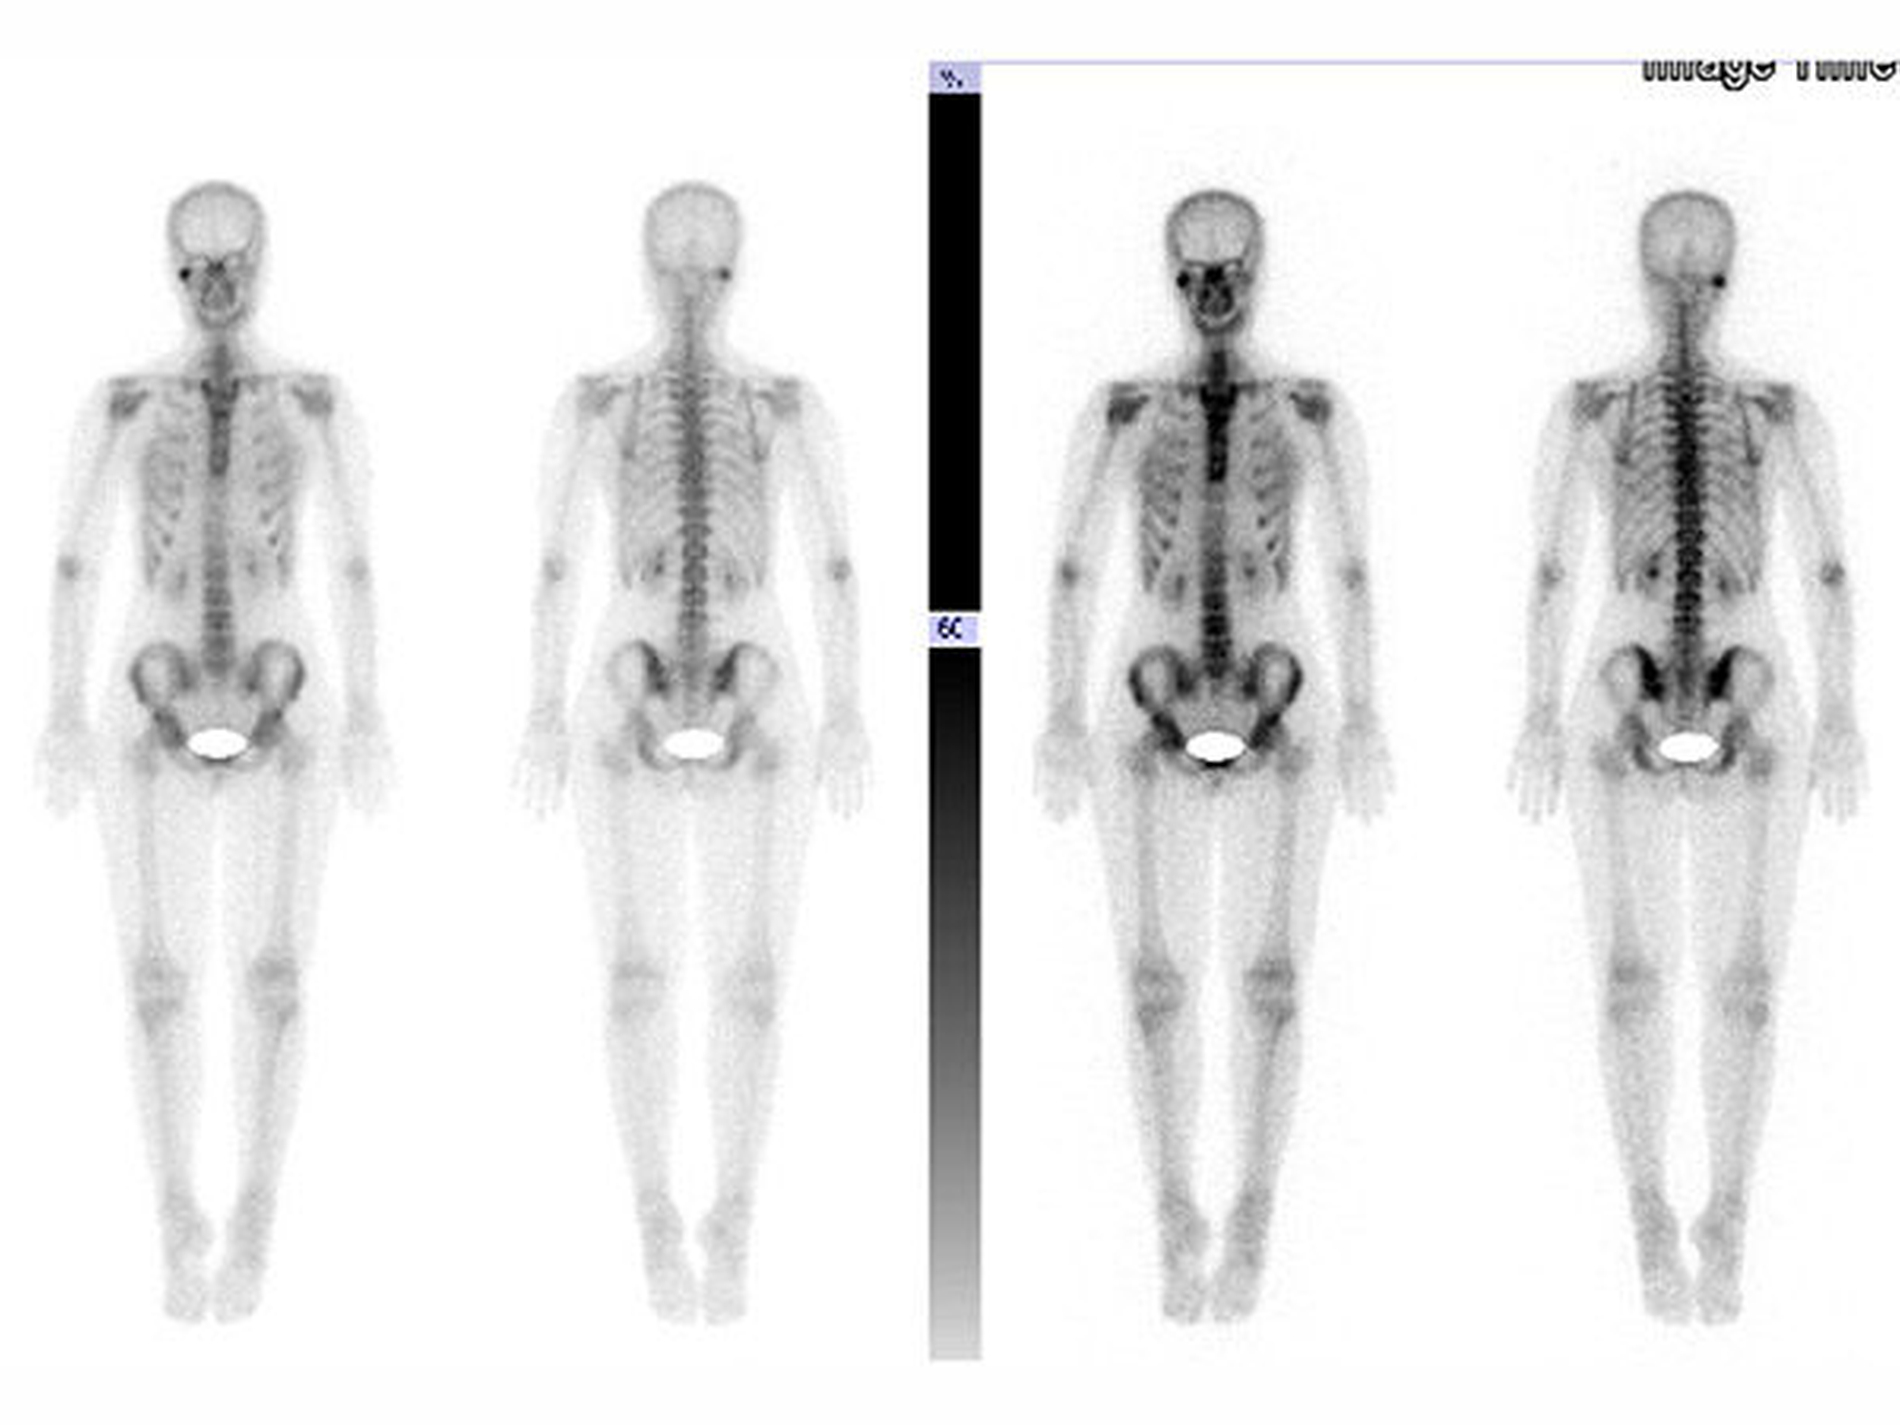

Mit Verdacht auf eine kondyläre Hyperplasie des rechten Unterkiefers wurde die Durchführung einer Skelettszintigrafie (Abbildung 3A) sowie einer CT-Bildgebung (Abbildung 3B) des Kiefers angeordnet. Hierbei konnte eine fokale Knochenstoffwechselanreicherung im Bereich des rechten Kiefergelenkköpfchens nachgewiesen werden. Die Kortikalis des rechten Kondylus war im Vergleich zur Gegenseite deutlich stärker ausgebildet, Hinweise auf eine tumoröse Raumforderung fanden sich in der CT nicht.

Die Patientin wurde in unsere ambulante Nachsorge entlassen. Geplant wurde eine Knochenszintigrafie zwölf Monate nach der Operation. Bei der letztmaligen ambulanten Vorstellung zwei Jahre postoperativ zeigte sich ein stabiler Befund. Die Unterkieferbeweglichkeit war uneingeschränkt, ein Kiefergelenksknacken rechts im terminalen Drittel der Mundöffnung hör- und spürbar. Beschwerden hatte die Patientin dadurch nicht. Die Okklusion war im Vergleich zum präoperativen Befund verbessert und stabil (Abbildung 6). In der Knochenszintigrafie konnte eine geringe Knochenstoffwechselsteigerung in Projektion auf das rechte Kiefergelenk festgestellt werden, dieses war vereinbar mit einem vermehrten postoperativen knöchernen Umbau.